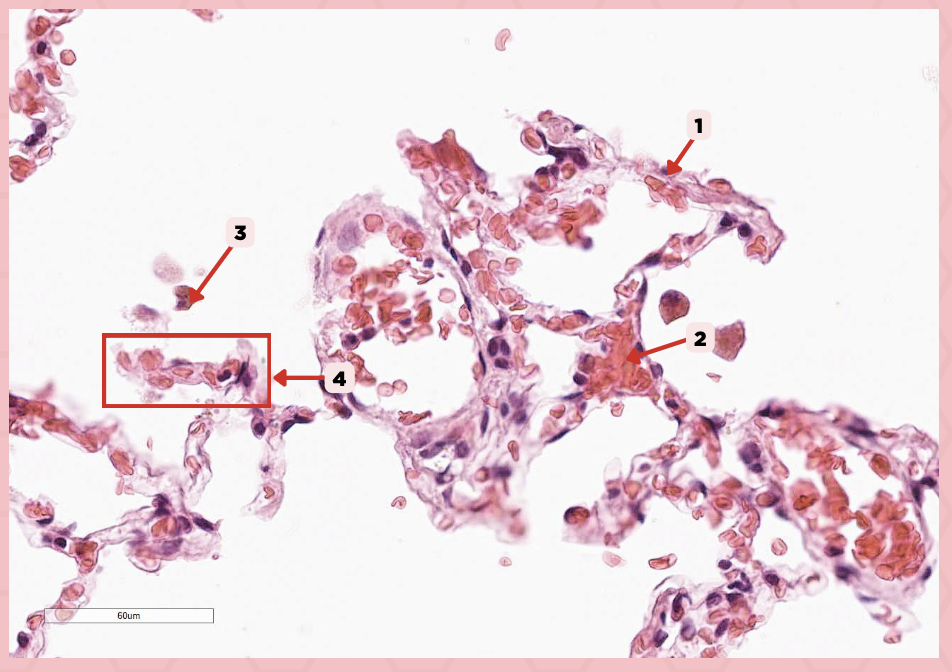

Interalveolar septum

Identify the structure labeled as 1.

Type I alveolar cell

Identify the structure labeled as 2.

Type II alveolar cell

Identify the structure labeled as 3.

Pulmonary Alveolar Macrophages (Dust Cells)

Identify the structure labeled as 4.

Pulmonary Alveolar Macrophages (Dust Cells)

What are the most numerous cells inside the alveoli?

Pneumocyte Type I

Which of the following labeled structures covers 95% of the alveolar surface?

Type I alveolar cell

Identify the structure labeled as 1.

Type II alveolar cell

Identify the structure labeled as 2.

Pulmonary Alveolar Macrophages (Dust Cells)

Identify the structure labeled as 3.

Endothelial Cells

Identify the structure labeled as 4.